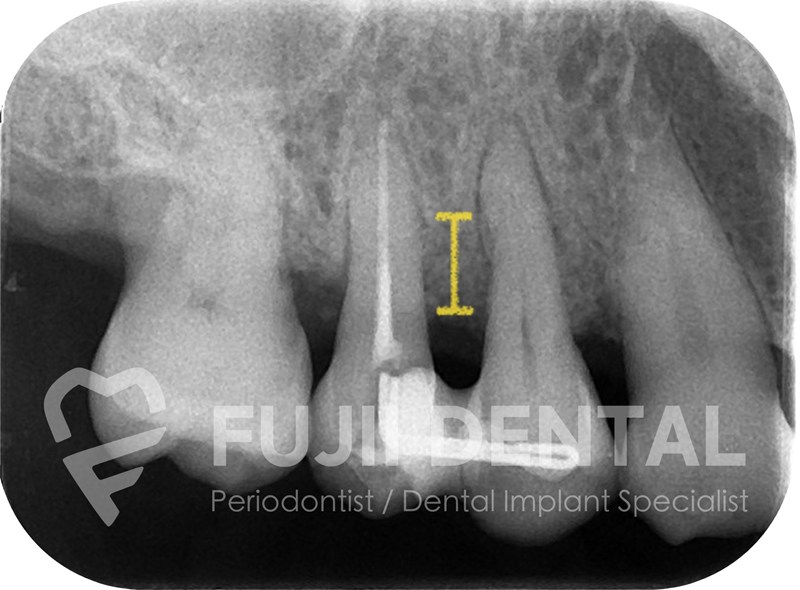

外科治療によって歯周病を止めた例です。歯周病にかかると歯を支える骨は減り続け、自然に止まることはありません。しかし、外科治療で骨の材料を歯のまわりに置くことで、骨の減少を食い止めるだけでなく、骨が作られる方向へと流れを変えることができます。こうして歯を支える骨が増えることで歯のグラつきが改善し、しっかり噛めるようになり、結果として歯の寿命を延ばすことにつながります。